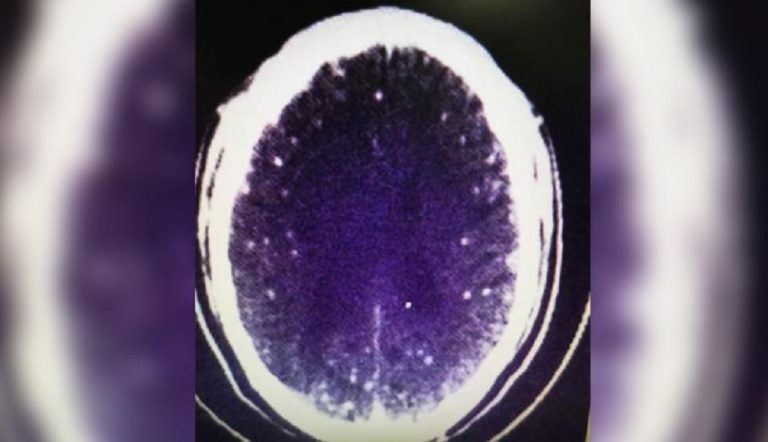

झु लाई अस्पताल लगेर सिटी स्क्यान गर्न लगाइयो उक्त सिटि स्क्यानको रिर्पोटमा दिमाखको तन्तुमा केहि खराबी देखियो । यो रिर्पोटले अस्पतालमा तरगं नै पैदा भयो चिकित्सकको टोलीले ती व्यक्तिमा अनुसन्धान गर्दै जादा सुगुर र खसीको मासु राम्ररी नपाकेर यो जुका सरेको हुनसक्छ भनेर प्रमाणित गरे ।

कसैले फित्ते जुकाको अण्डा खाएमा परिजीवीको संक्रमणबाट न्युरो सिस्तिसर्कोसिस हुन्छ । मानिसमा यो खाद्यपदार्थको माध्यमबाट फित्ते जुका शरीर भित्र पुगेपछि संक्रमण उत्पन्न हुन्छ । यो तन्तु जस्तै मांशपेशी ,लार्भा र मस्तिष्कमा पुग्छ र त्यहाँ सिस्ट बनाउँछ ।

यो सिस्ट मस्तिष्कमा पुगेको अवस्था न्युरो सिस्टिसर्कोसिस हो । यो रोगको संक्रमण विशेष गरि सुगुर डुल्ने ठाँउमा जहाँ सरसफाई कम हुने ठाँउमा बढी देखिने बताइएको छ ।